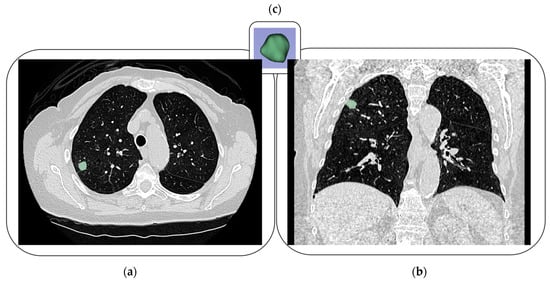

Background: Uterine malignancies frequently metastasize to the lungs. Pulmonary metastasectomy has demonstrated survival benefits in some malignancies; however, its efficacy for uterine malignancies remains unclear. Methods: We retrospectively analyzed 38 patients who underwent pulmonary metastasectomy for uterine malignancies at the Kanagawa Cancer Center between 2010 and 2020. The primary endpoint was recurrence-free survival (RFS) after pulmonary resection. Results: The median patient age was 63 years. The primary sites were the cervical uteri (n = 22) and corpus uteri (n = 16). The FIGO stages at the time of treatment for the primary tumor were I, II, III, IV, and unknown in 20, 7, 9, 1, and 1 patient, respectively. The median disease-free interval (DFI), defined as the interval between primary treatment and first recurrence, was 26.5 months. Most patients had single metastasis (n = 32). The procedures for metastasectomy included lobectomy, segmentectomy, and wedge resection (n = 15, 8, and 15, respectively), and two cases resulted in microscopically incomplete resection. The median follow-up period after pulmonary metastasectomy was 57 months, with 16 patients experiencing recurrence after pulmonary metastasectomy (5-year RFS rate: 55.6%). Univariate analysis identified FIGO stage ≥ III, DFI < 12 months, presence of synchronous extrapulmonary recurrence, and uterine sarcoma as poor prognostic factors. No prognostic differences were found between cervical and corpus uteri cancers. Conclusions: Pulmonary metastasectomy may confer prognostic benefits in patients with uterine malignancies. Careful consideration is warranted for patients with advanced-stage primary tumors, early recurrence after primary treatment, synchronous extrapulmonary recurrence, and uterine sarcoma.